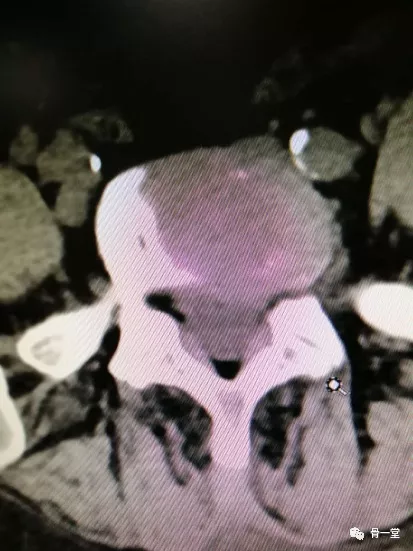

患者沈某,女,70歲,腰痛伴左下肢不適間作20年,加重伴左下肢麻痛2天,門診CT、MR提示腰4/5-腰5/骶1椎間盤向左側突出並壓迫神經。